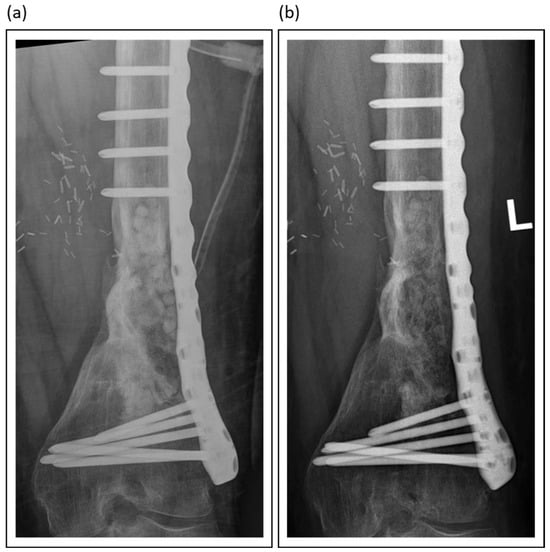

Among synthetic grafts, ceramic-based materials, particularly those combining calcium sulphate with hydroxyapatite, such as PerOssal® or Cerament®, have demonstrated promising outcomes. The inclusion of hydroxyapatite mitigates the early resorption of calcium sulfate, enhances biocompatibility, and reduces inflammatory responses, all while serving as a durable scaffold for bone regeneration [87,96]. Figure 4 presents an example of the use of absorbable PerOssal® beads.

Figure 4.

PerOssal® as part of the treatment of chronic osteomyelitis in a distal femur: (a) Postoperative X-Ray image; (b) Follow-up X-Ray 2 years later. The PerOssal®-Beads are largely resorbed. No recurrence of infection was detected clinically.